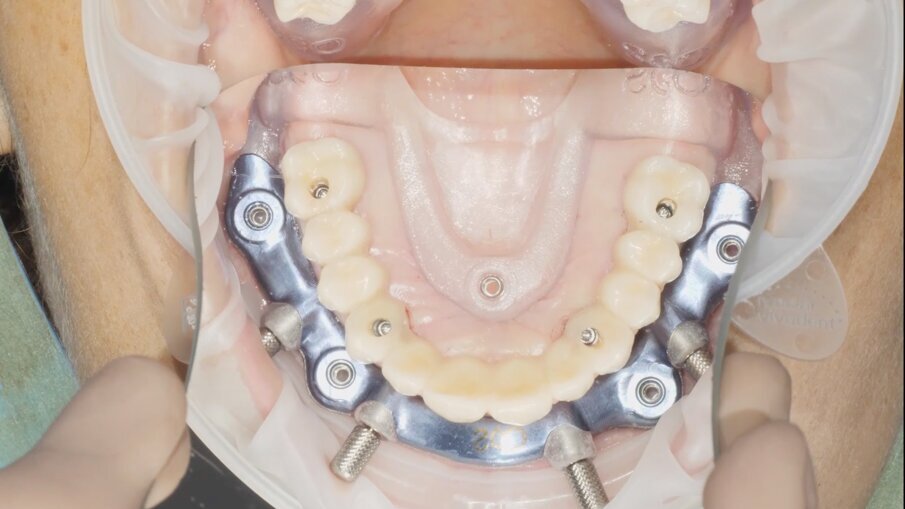

Il posizionamento implantare segue un ordine contrapposto, prestando attenzione nella fase di avvitamento a non arrivare subito a fine battuta sulla dima implantare (Figg. 14, 15). I mounter montati sugli impianti monofasici con MUA integrato devono essere inseriti all’interno delle cannule della dima implantare, prima di procedere a ricercare l’accoppiamento tra il mounter stesso e lo scasso sulla dima che permette l’accesso del cacciavite per il rilascio (Figg. 16-18). Questo accorgimento ci dà la conferma ulteriore del corretto posizionamento degli impianti con MUA integrato da 17° di inclinazione e non è previsto per i dispositivi con MUA integrato con inclinazione 0°. Una volta rimossi i mounter possiamo disancorare la dima chirurgica dalla dima base (Fig. 19). La Fig. 20 mostra l’emergenza della componente protesica integrata degli impianti attraverso la mucosa. Sui MUA vengono quindi posizionati gli abutment in titanio preparati dal tecnico che ha potuto seguire la chirurgia sul modello (Fig. 21).

21